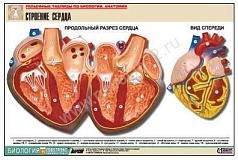

Комплект включает в себя 21 таблицу следующего содержания:

19. Строение сердца;